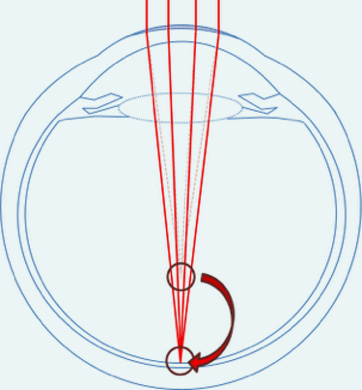

La myopie est le trouble affectant la netteté de la vision de loin. Elle se manifeste chez le sujet dont l'oeil est trop long par rapport à sa puissance. Les rayons lumineux provenant d'un objet lointain vont alors converger en avant de la rétine, sur laquelle l'image formée sera floue !

Plus le degré de myopie sera important, au plus la distance de l'oeil à laquelle il est possible de voir net sera réduite. Cette distance peut se calculer en première approximation comme l'inverse du degré de la myopie. Ce degré se quantifie en dioptrie (D), et fait référence à la puissance du verre qu'il faut placer en face de l'oeil pour que la vision redevienne nette. L'oeil étant trop convergent, le verre devra être au contraire divergent d'où l'utilisation d'un signe négatif.